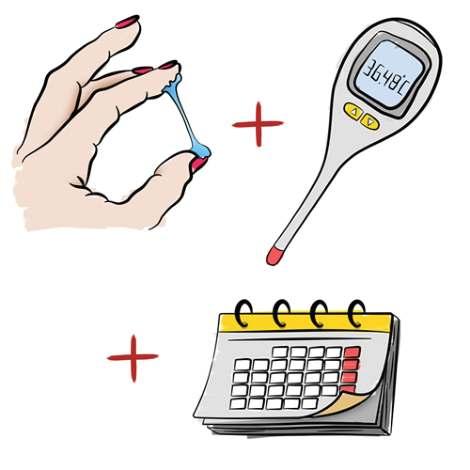

Los métodos naturales de conocimiento de la fertilidad se basan en la observación de síntomas asociados a los procesos fisiológicos que dan lugar a la ovulación, y en la adaptación del acto sexual a las fases fértiles o infértiles del ciclo

menstrual en función de que se desee o no una concepción, sin el uso de fármacos, procedimientos mecánicos ni quirúrgicos, los métodos anticonceptivos hormonales utilizan hormonas